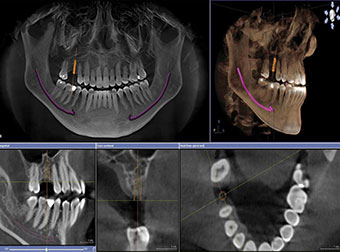

CBCT/OPG

IN-HOUSE CBCT & OPG

CBCT (cone-beam computed tomography) scan is a type of medical imaging technique that produces precise 3D images of the bones and soft tissues in the maxillofacial region.

CBCT scan can give a detailed picture (2D sections and 3D structures) of teeth, jaws, TMJ, airways, sinuses, nasal cavity, orbits, and other surrounding anatomical structures of the head and neck region.

There are many benefits to getting a CBCT scan:

Better image quality and accuracy

Provides comprehensive information about your oral health

Comfortable and quick experience

A lower dose of radiation

It is used as part of the planning step for your dental treatment. By having a CBCT scan, your dentist will be able to have much-needed detailed information about your oral situation. This information can include images of:

Bone loss

Tooth Decay

Nerves

Soft Tissues

Facial Fractures or Abnormal Growths

Infections

Tooth Root Issues

Signs of TMJ or other problems

Other Irregularities

It is mandatory to do a CBCT before implant placement, as it is the most reliable way to do a 3D planning.